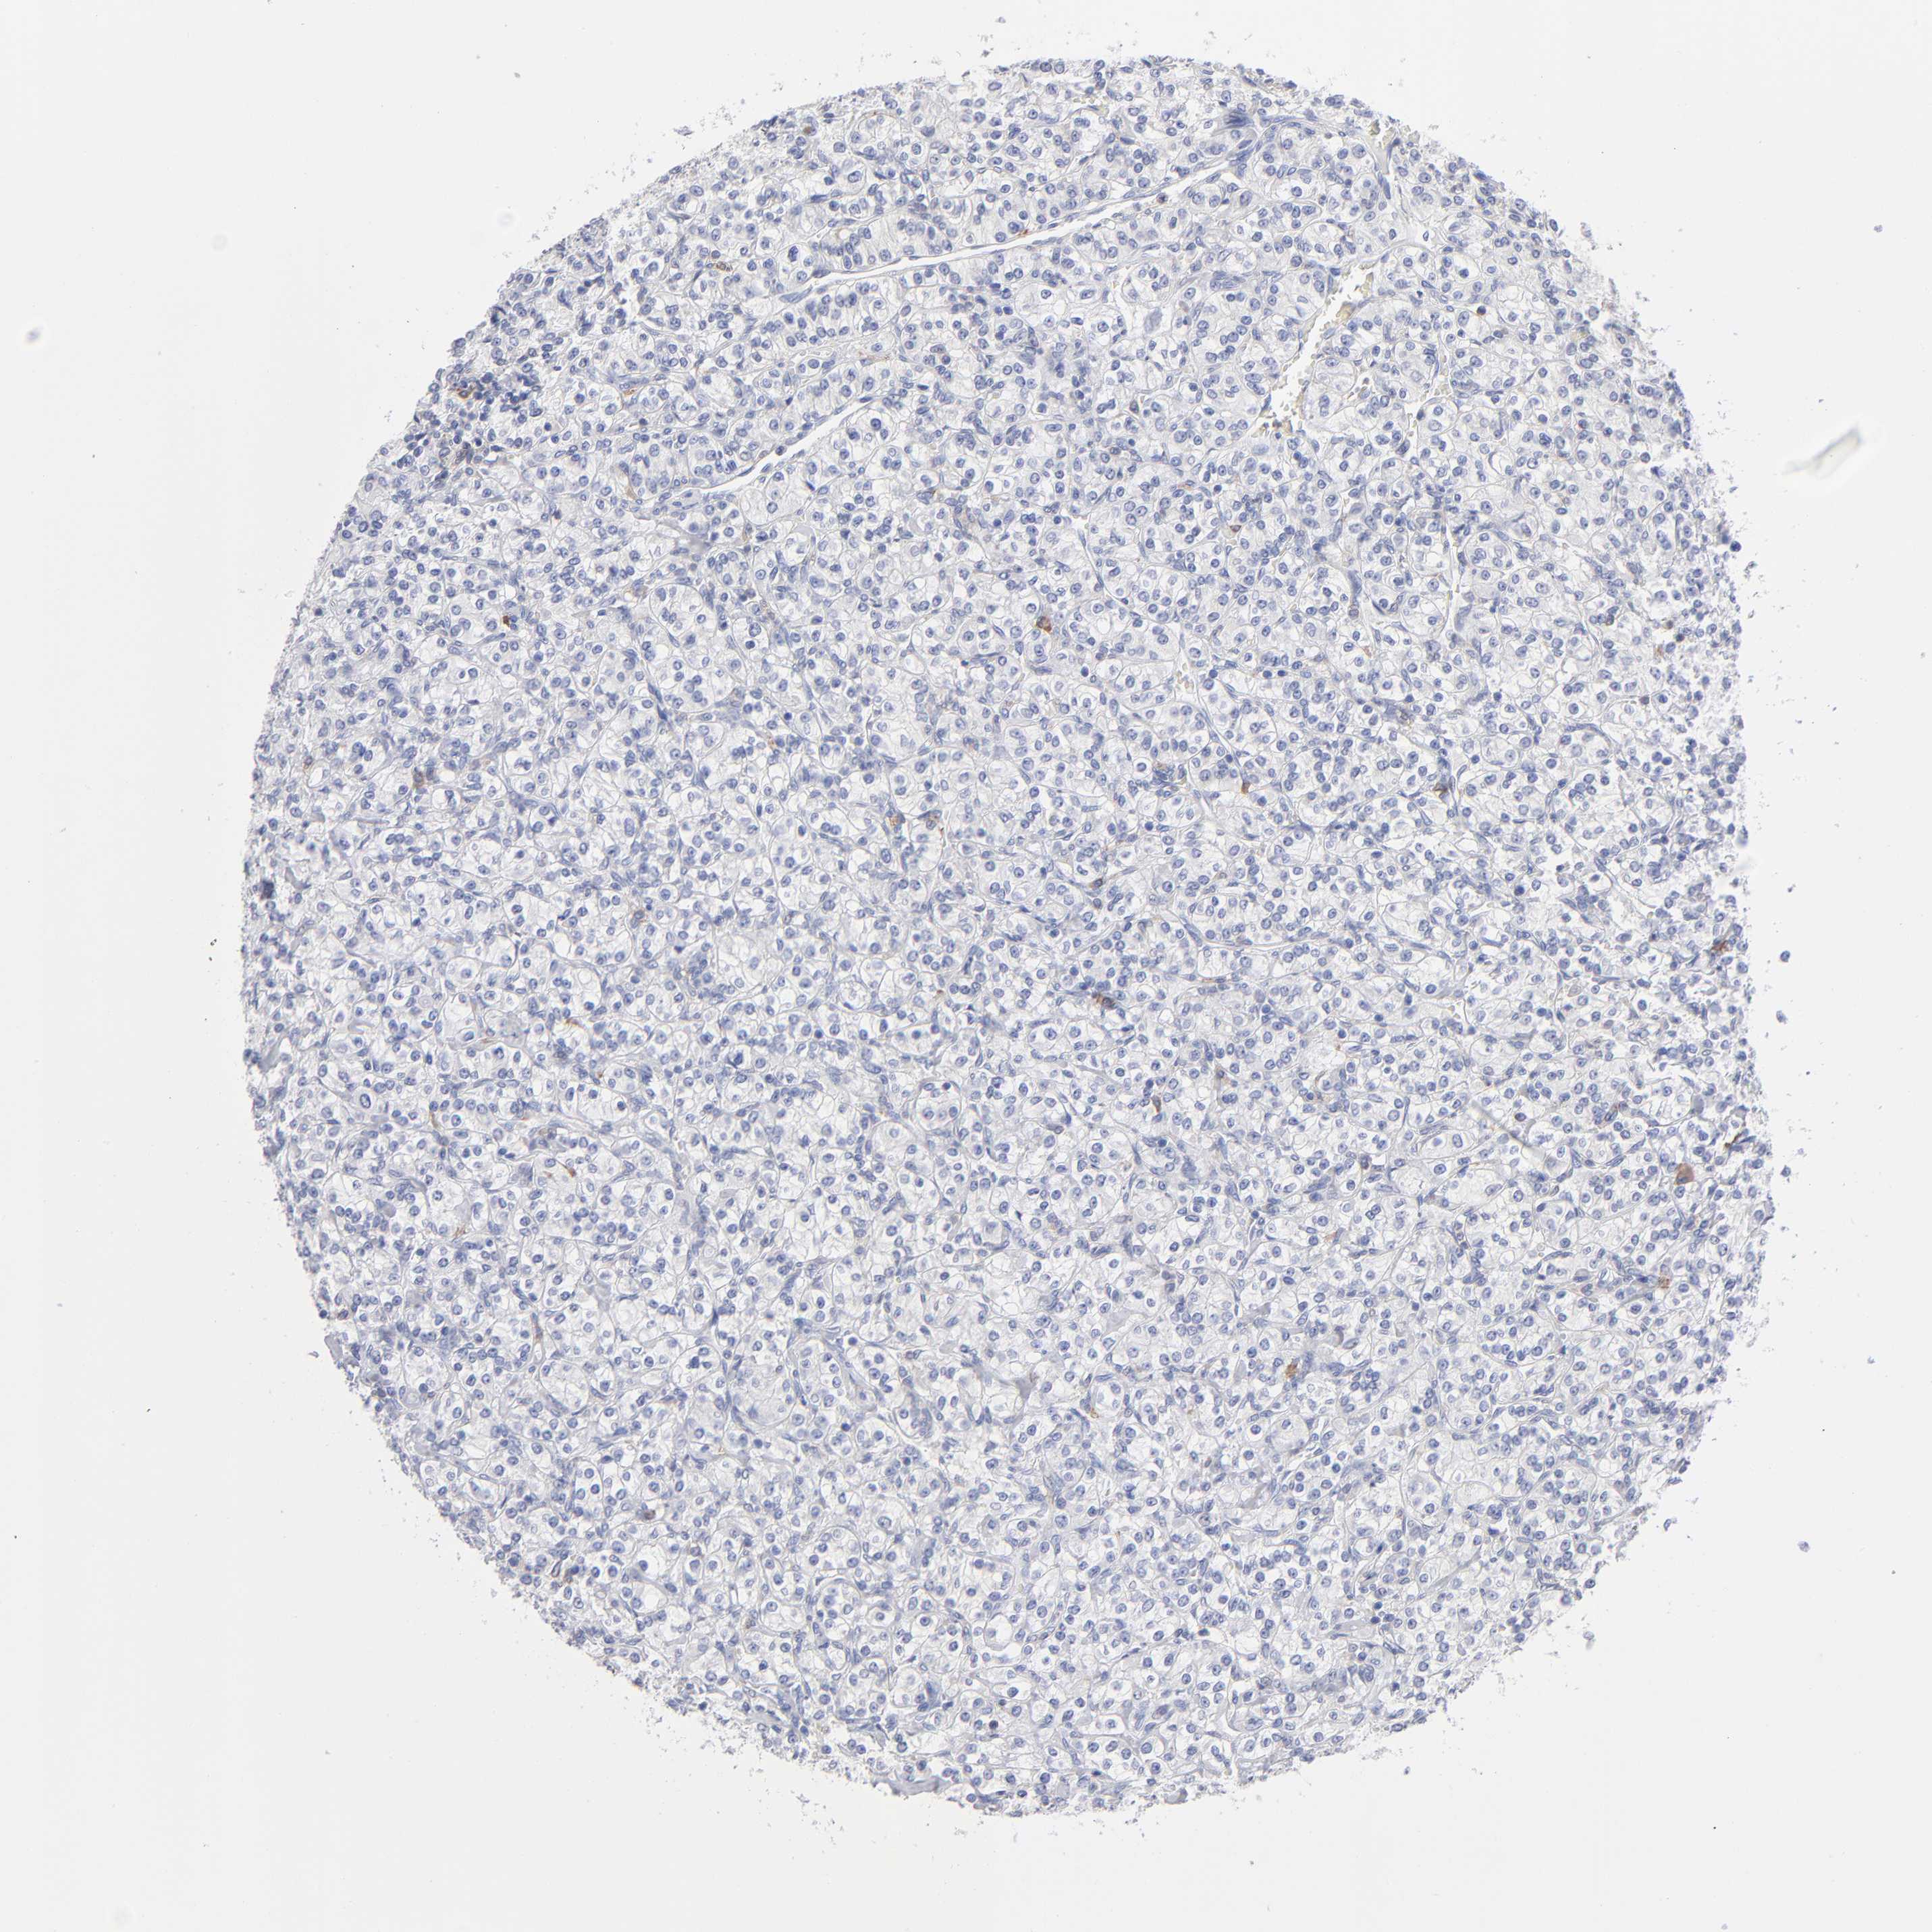

Renal cancer

Kidney chromophobe